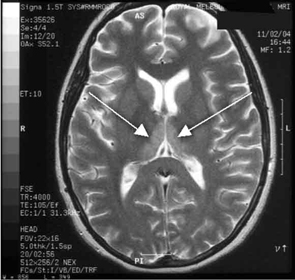

Haematological and biochemical test results were largely normal, but her serum levels of creatinine (0.04 mmol/L; normal range [NR], 0.05–0.10 mmol/L) and urea (2.2 mmol/L; NR, 2.5–6.1 mmol/L) were slightly low, and her INR (international normalised ratio) was 2.0 (NR, 0.8–1.2). There were also some elevated levels in her liver function test results: γ-glutamyl transferase, 60 U/L (NR, < 50 U/L); alanine aminotransferase, 486 U/L (NR, < 55 U/L); and bilirubin, 32 U/L (NR, 0–19 U/L). Cerebrospinal fluid (CSF) examination and magnetic resonance imaging (MRI) were also undertaken to exclude intracranial causes. The CSF findings were normal, but the MRI revealed bilateral thalamic lesions (Figure 2).

Given the new clinical features and her MRI result, a diagnosis of Wernicke’s encephalopathy was made. Thiamine deficiency was suspected to be secondary to hyperemesis gravidarum. Interestingly, her serum thiamine level was only marginally low at 64 nmol/L (normal range, 66–200 nmol/L). Therapy with pyridoxine, folic acid and intravenous thiamine replacement was commenced.

Our case is unusual in that visual deterioration was the first symptom of an evolving thiamine deficiency. There was a delayed presentation of the classical triad of Wernicke’s encephalopathy — ataxia, mental confusion and ocular gaze problems. Moreover, in our case, MRI scanning was able to detect sensitive neurological changes, raising the suspicion of thiamine deficiency. This information was important in prompt treatment of the condition when clinical signs began to emerge. Indeed there are reports of the usefulness of MRI imaging in diagnosing cases of Wernicke’s encephalopathy.7